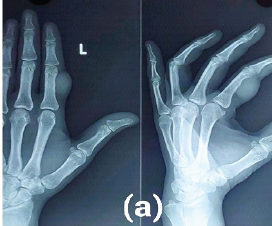

Giant Cell Tumor of the Tendon Sheath: Case Series and Review of Literature

Naman K Parakh , S Krishna Kumar , Siddharth Jain , Parin Shah

………………………………p.256-260